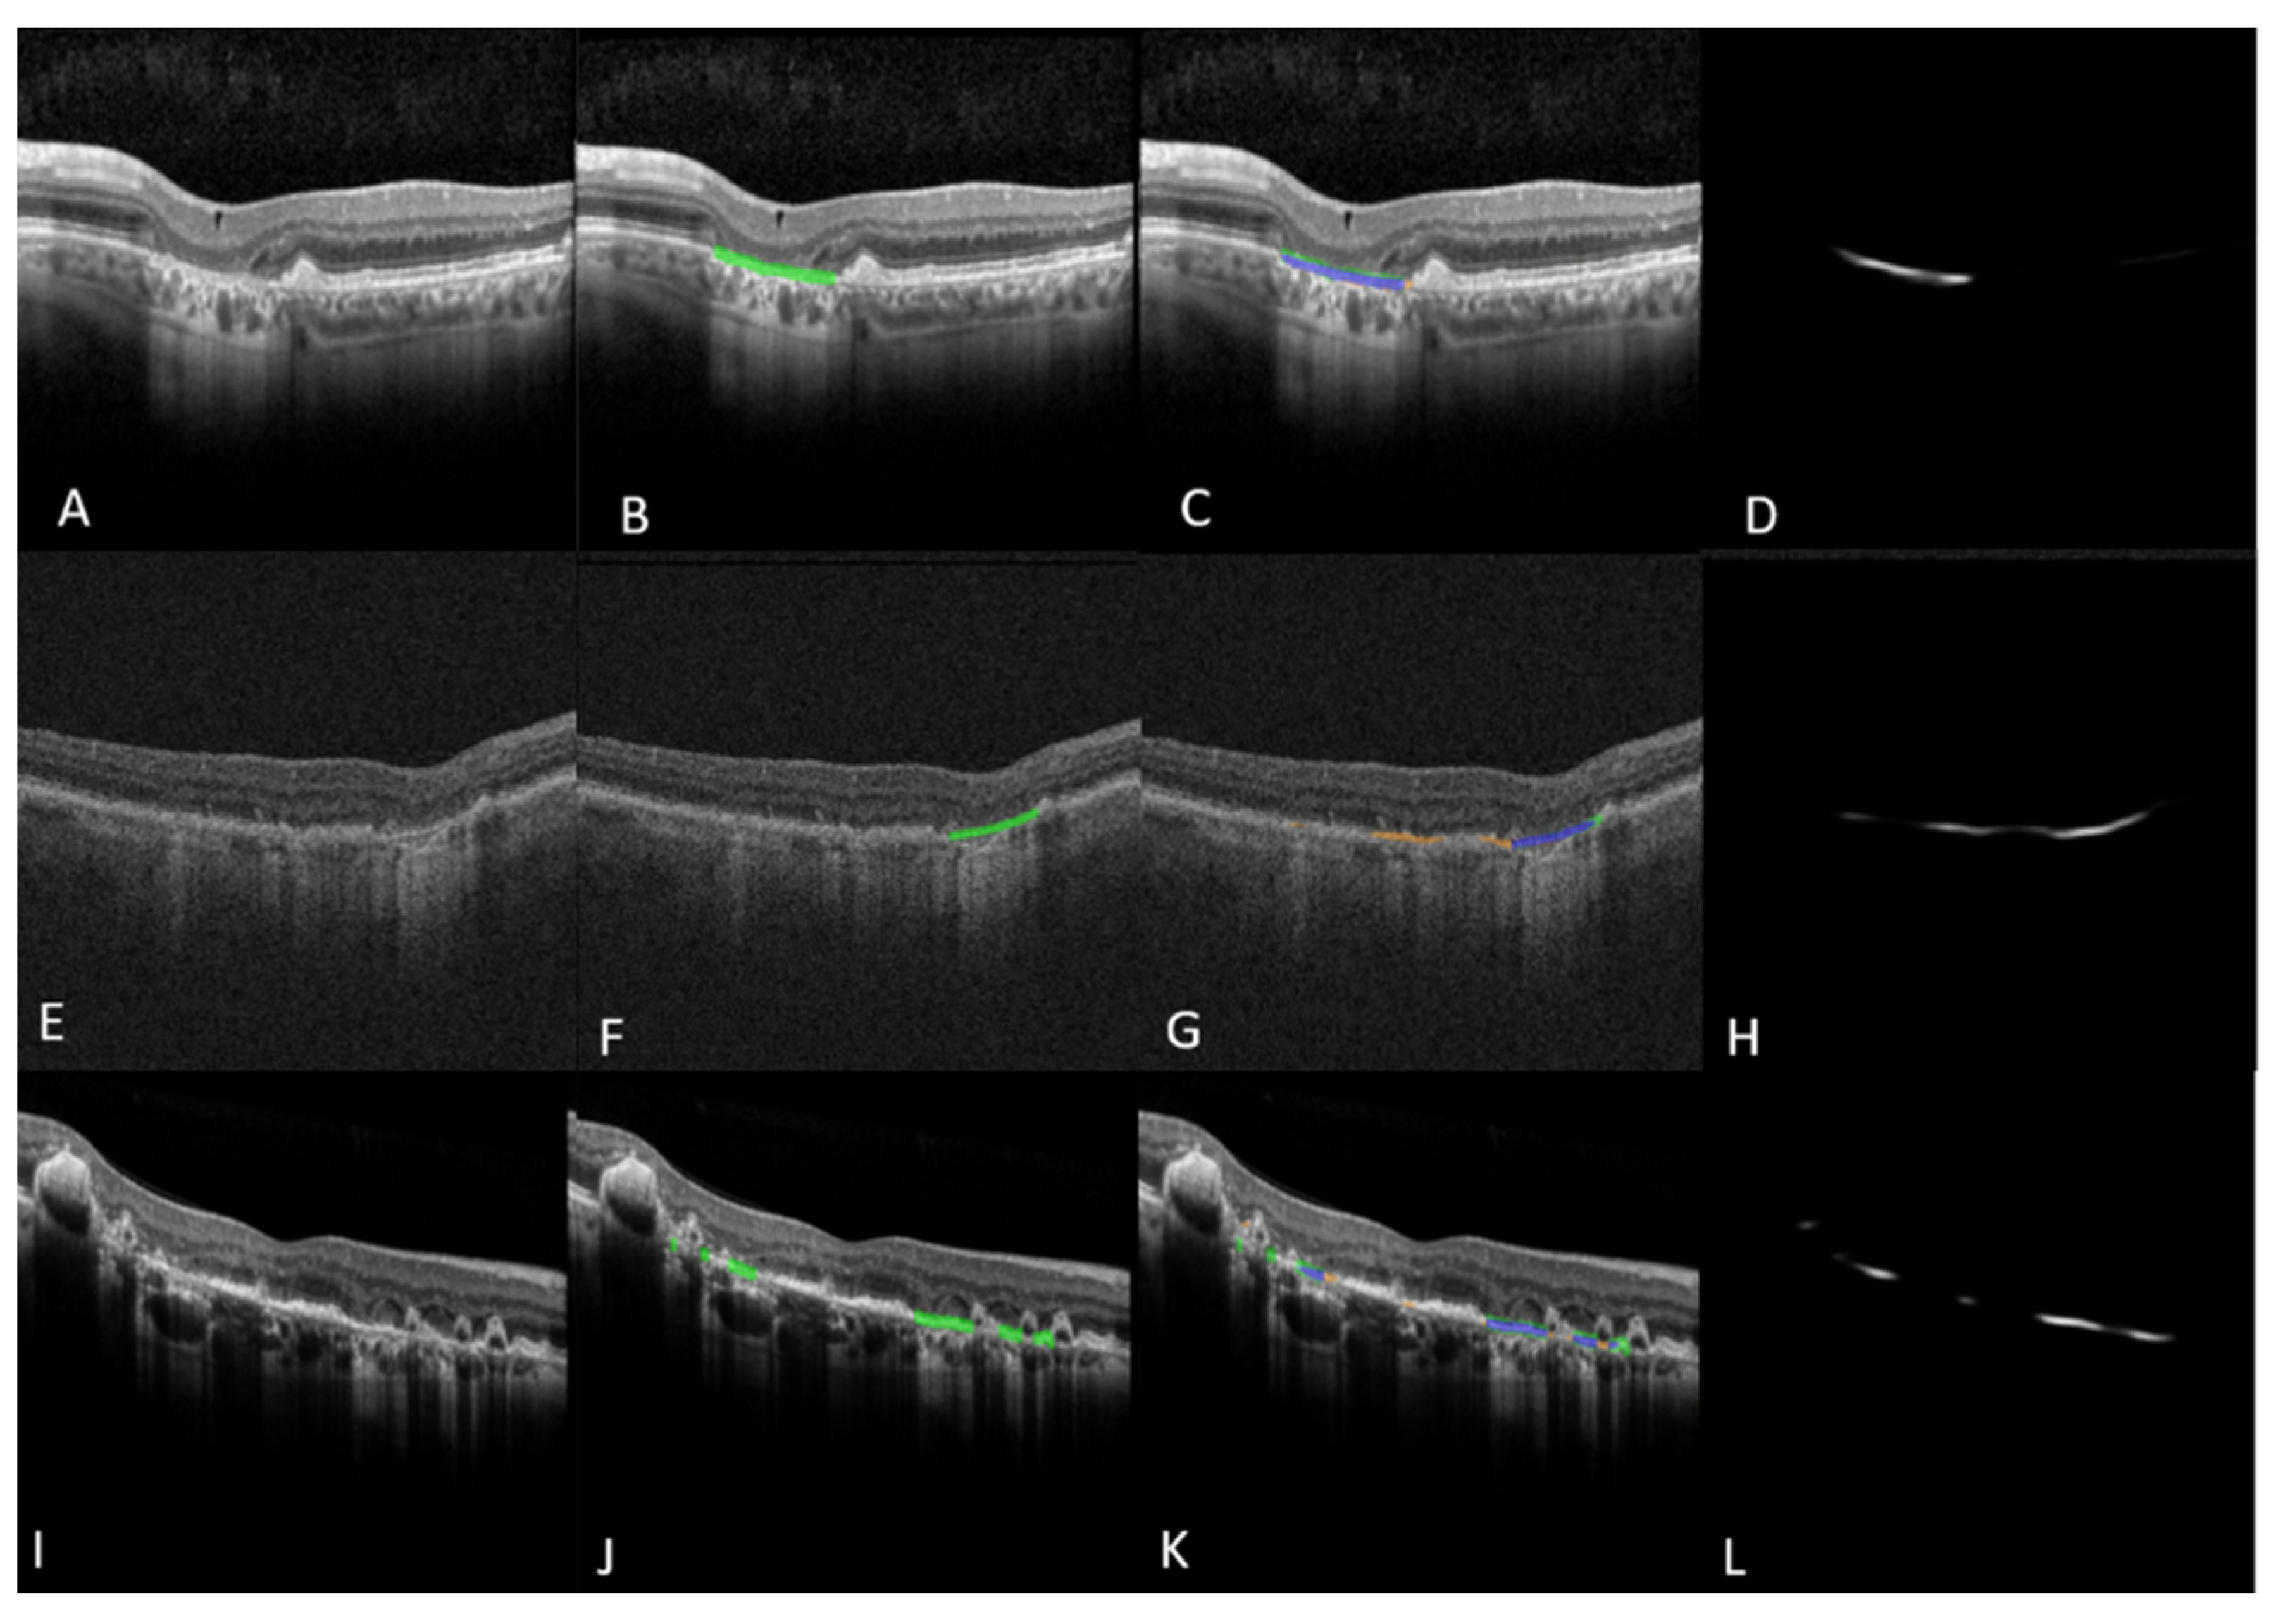

Figure 4.

Left panel (A–D) shows B-Scan model GA segmentation performance as visualized on individual B-Scans of an OCT volume. (A) Raw B-scan from a patient with GA; (B) Ground truth mask (indicated in green) generated using multi-layer segmentation and concurrence of EZ, RPE, and BM lines; (C) B-scan model output overlay with blue areas indicating correct segmentation of GA area, orange areas indicating false positive segmentation and green areas indicating false negative segmentation; (D) Gray-scale output of the B-scan model indicating model confidence. Middle panel (E–H) shows an example of false positive segmentation. Right panel (I–L) shows an example of false negative segmentation. GA: Geographic Atrophy; EZ: Ellipsoid Zone; RPE: Retinal Pigment Epithelium; BM: Bruchs Membrane. Images A–C and I–K were captured using Spectralis HRA+OCT (Heidelberg Engineering, Heidelberg, Germany) with the 97 B-scan macular cube protocol. Images E-G were captured using or Cirrus HD-OCT (Zeiss, Oberkochen, Germany) with the 512 × 128 imaging protocol for 6 mm × 6 mm macular cubes.